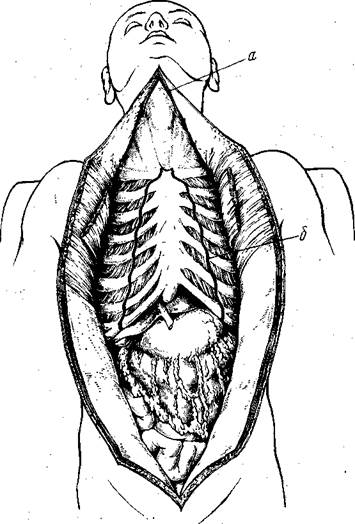

Таким образом, полость живота оказывается широко раскрытой, грудная клетка освобождена от кожи и мышц, шея — от кожи, а отделенные покровы торса в виде огромных лоскутов отвернуты в стороны (рис. 27).

Рис. 27.

а—разрезы для извлечения языка, глотки, гортани; б—линии рассечения реберных хрящей и грудино-ключичных сочленений.